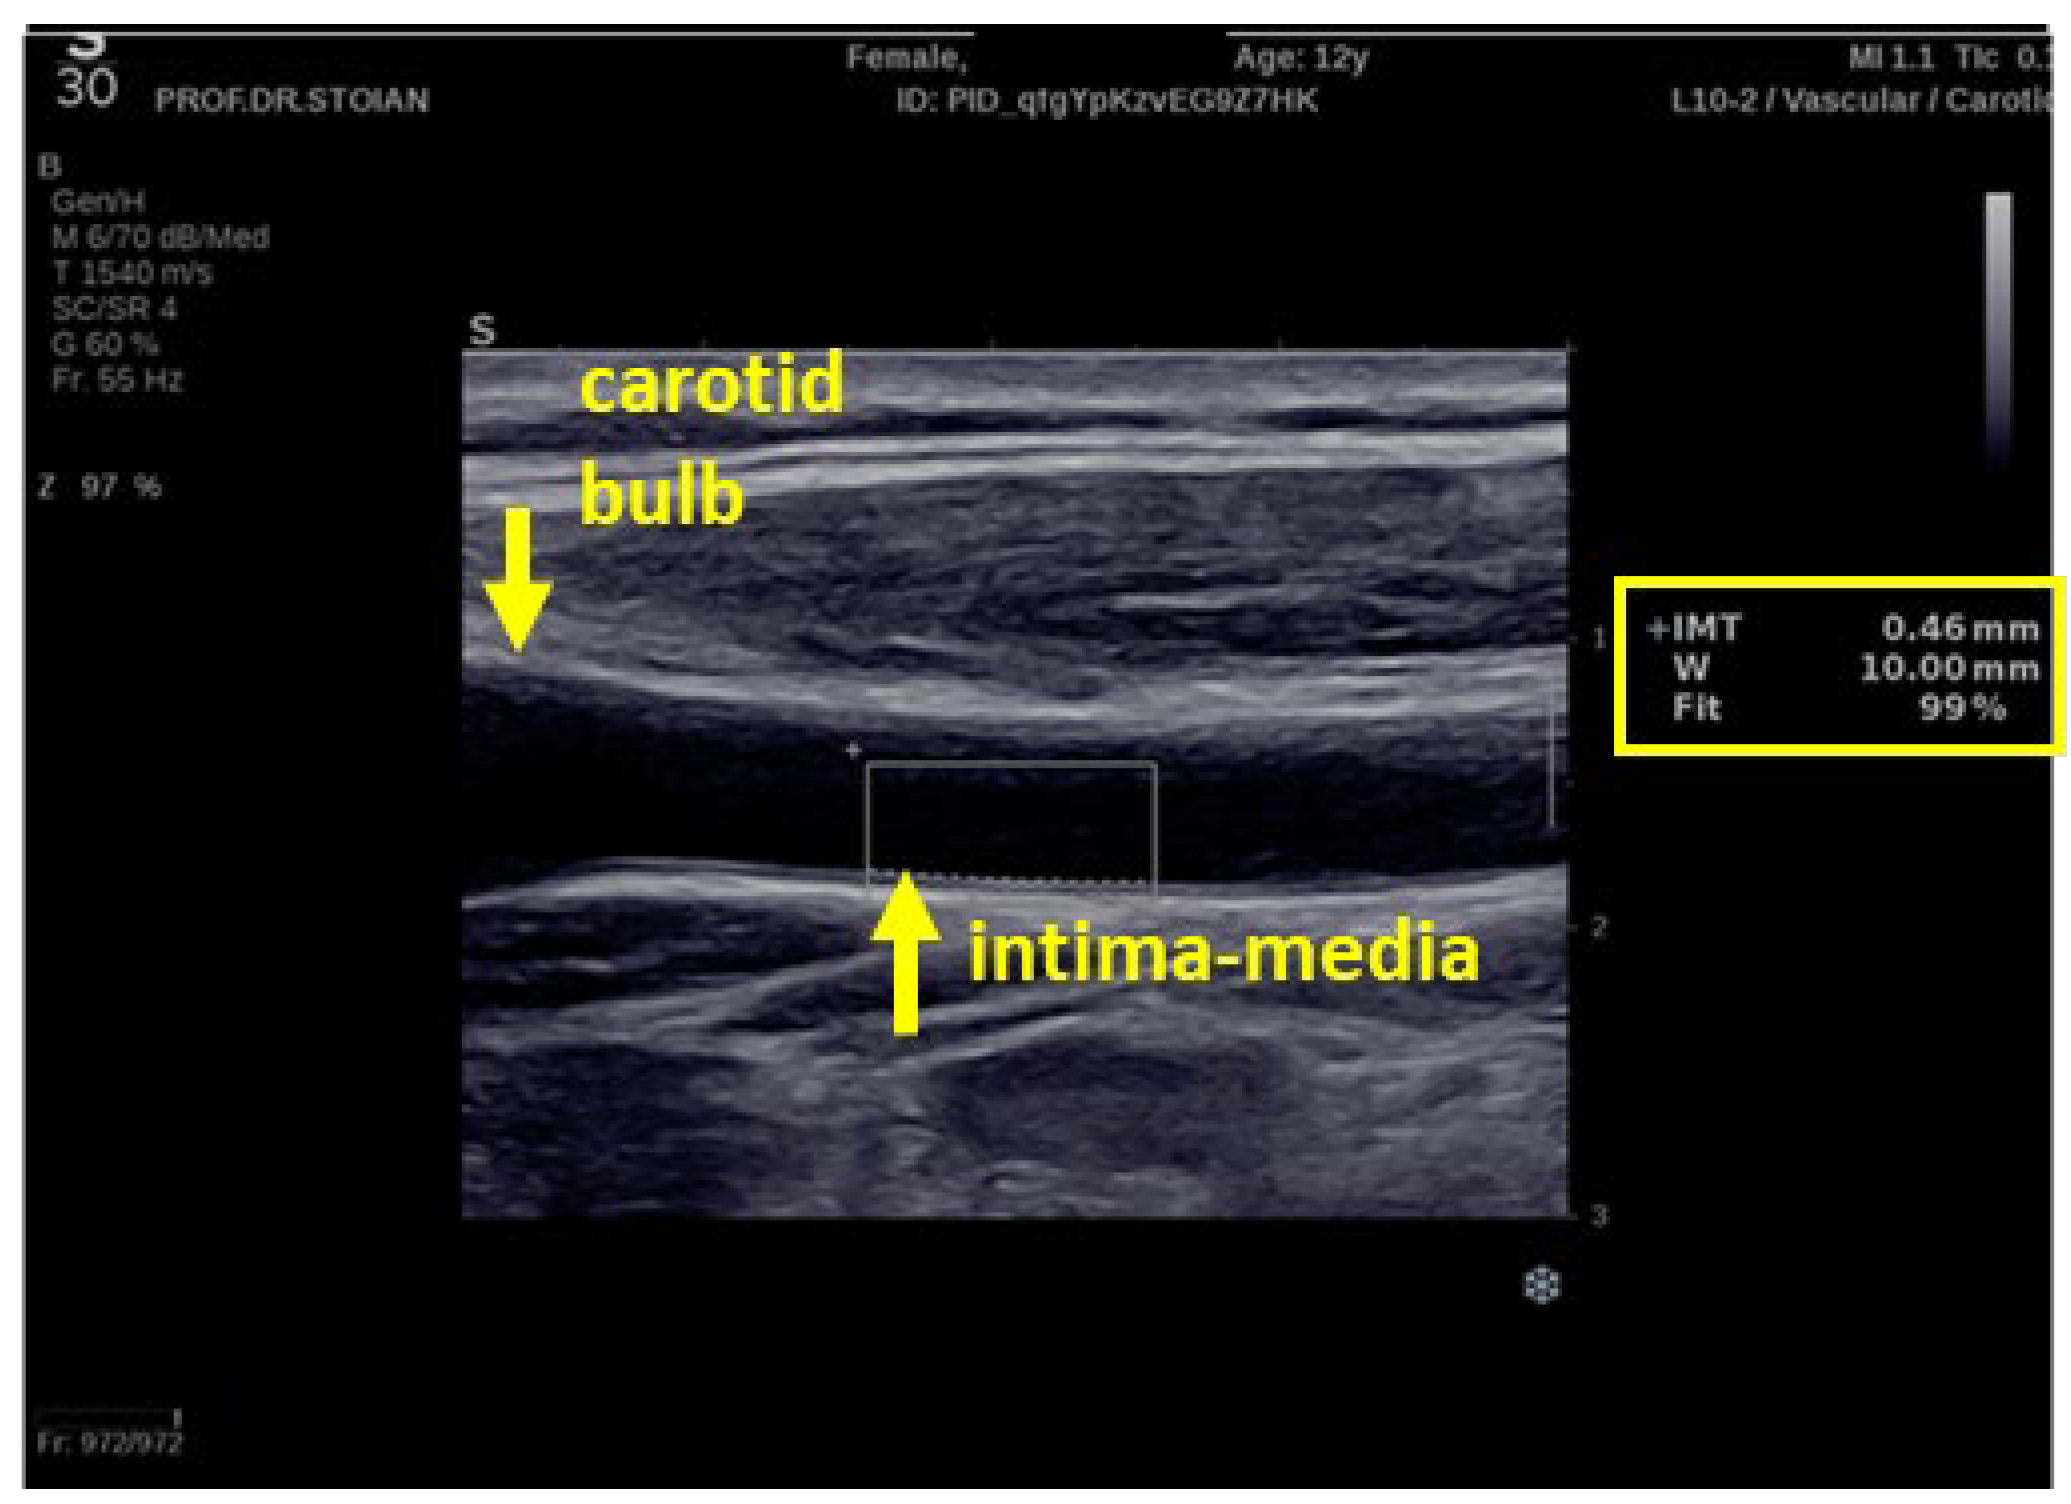

2.4. The Carotid Intima-Media Thickness Measurement

- The ultrasonography technique